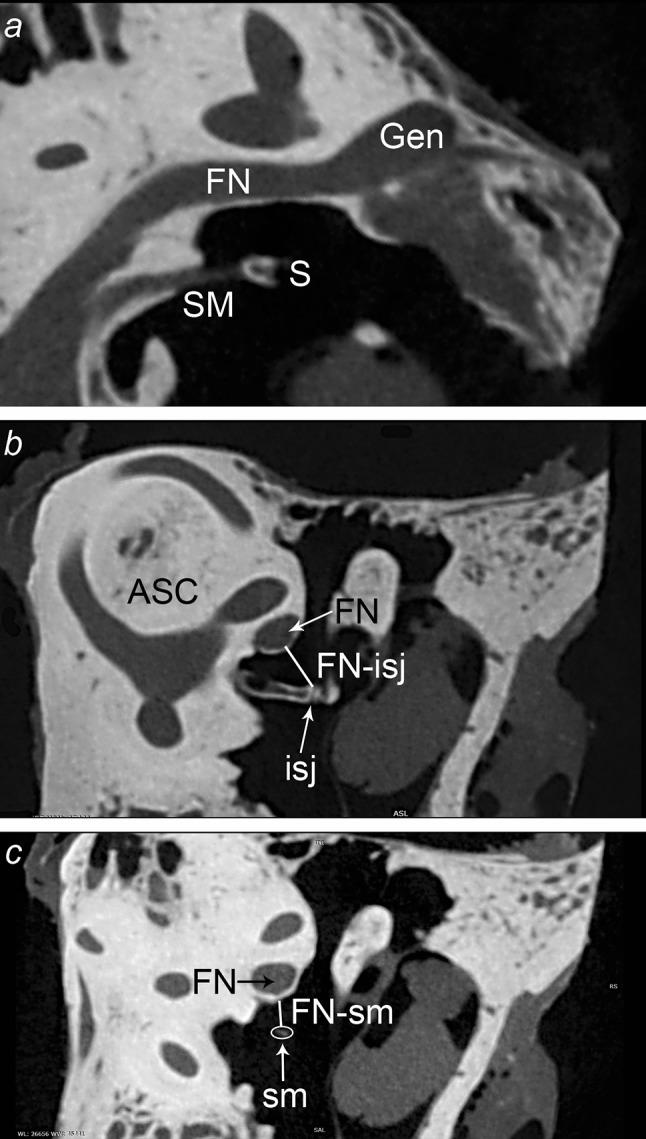

The aim of this study was to evaluate the morphology of the stapedius muscle and its tendon with the use of microCT and to describe their anatomic relationship with facial nerve and incudostapedial joint. The study was performed on 16 fresh cadaveric temporal bones scanned in microtomography (microCT). Stapedius muscle and its tendon were identified in each set of images. The length of the medial and lateral border of the stapedius tendon (STL-med, STL-lat), width at the insertion to stapes (STW-s), at the point it emerges from the pyramidal eminence (STW-p) and in the half way from the pyramidal eminence to stapes (STW-m), and the length and the width of the belly of stapedius muscle (BSML and BSMW) were measured in modified axial plane. The shortest distance between the facial canal and incudostapedial joint (FN-isj), and between the facial canal and stapedius tendon (FN-st) were measured in the Pöschl plane. The average values of all distances measured were: STL-lat 1.29 ± 0.50 mm, STL-med 1.27 ± 0.44 mm, BSML 2.98 ± 0.51 mm, STW-s 0.47 ± 0.10 mm, STW-p 0.46 ± 0.12 mm, STW-m 0.35 ± 0.12 mm, BSMW 1.26 ± 0.29 mm, FN-isj 1.72 ± 0.33 mm, FN-st 1.35 ± 0.30 mm. The stapedius muscle complex consists of the tendon and the belly, and the border between them in microCT scans is not always evident. The distance between the facial nerve and the incudostapedial joint is greater than the distance between the facial nerve and the stapedius muscle tendon.

本研究的目的是利用显微CT评估镫骨肌及其肌腱的形态,并描述它们与面神经及砧镫关节的解剖关系。本研究对16个新鲜尸体颞骨进行了显微断层扫描(显微CT)。在每组图像中识别出镫骨肌及其肌腱。在改良的轴位平面上测量镫骨肌腱内侧和外侧边界的长度(STL-med、STL-lat)、在镫骨插入处的宽度(STW-s)、从锥隆起处穿出点的宽度(STW-p)以及在从锥隆起至镫骨中途点的宽度(STW-m),以及镫骨肌肌腹的长度和宽度(BSML和BSMW)。在Pöschl平面上测量面神经管与砧镫关节之间(FN-isj)以及面神经管与镫骨肌腱之间(FN-st)的最短距离。所有测量距离的平均值为:STL-lat 1.29±0.50毫米,STL-med 1.27±0.44毫米,BSML 2.98±0.51毫米,STW-s 0.47±0.10毫米,STW-p 0.46±0.12毫米,STW-m 0.35±0.12毫米,BSMW 1.26±0.29毫米,FN-isj 1.72±0.33毫米,FN-st 1.35±0.30毫米。镫骨肌复合体由肌腱和肌腹组成,在显微CT扫描中它们之间的边界并不总是清晰可见。面神经与砧镫关节之间的距离大于面神经与镫骨肌腱之间的距离。